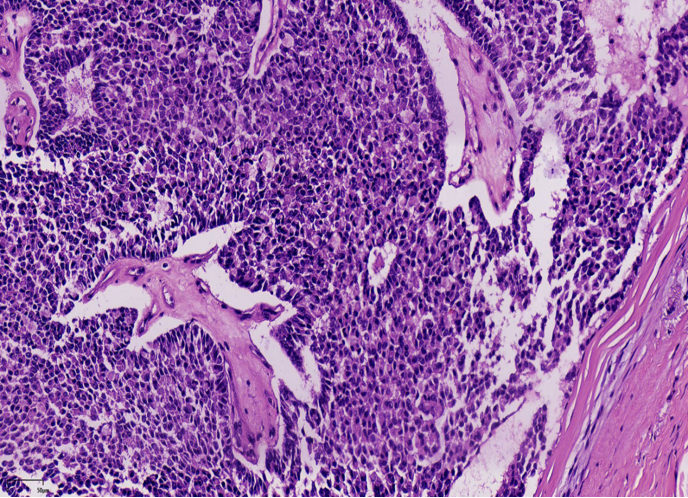

结构特点:轮廓清楚的实性结节纤细的血管轴心。

纤细的脉管轴心

纤细的血管轴心周围细胞呈栅栏状排列

1、浸润性实性乳头状癌:保留实性乳头状结构,体积大的团巢,轮廓不规则,间质促纤维反应,肌上皮缺失,原位SPC背景

2、实性乳头状癌伴浸润:轮廓圆滑的结节,伴有浸润性成分,包括粘液癌,NET,浸润性癌(NST)

SPC+富于细胞的黏液癌

浸润性SPC